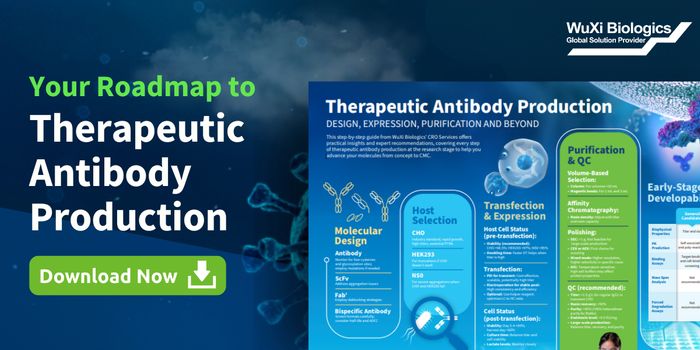

JUL 23, 2025Drug Discovery & DevelopmentDrug development and production rely on stringent quality controls, reproducibility, and verification. Biopharmaceutical ...